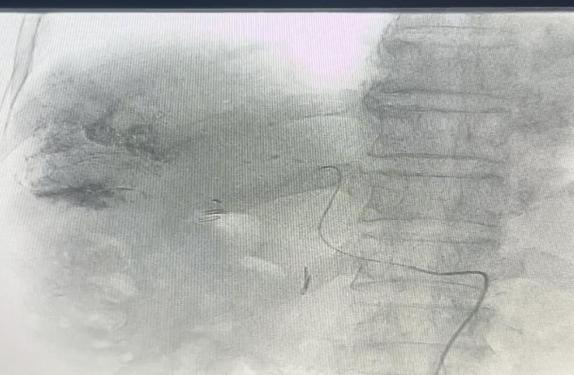

通过DSA造影找出显影的肿瘤供血动脉

微导管超选找到肿瘤供养血管,透视下缓慢注入碘油化疗栓塞乳剂及栓塞微球栓塞肿瘤责任血管

术后显示肿瘤供血动脉减少、消失,瘤体内碘油乳剂沉积良好